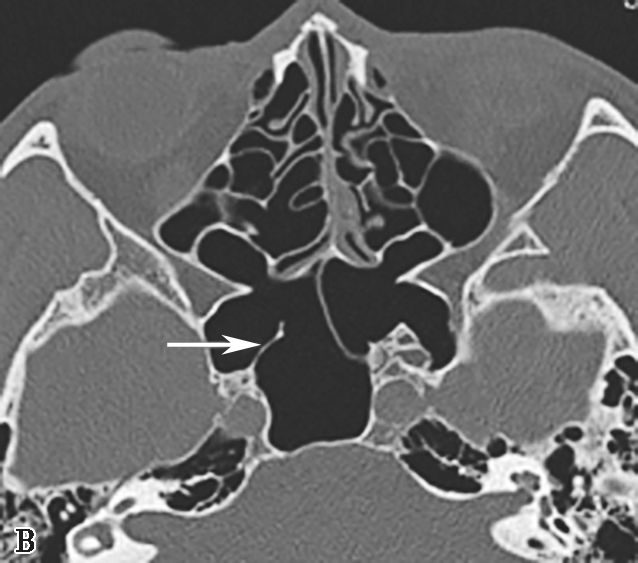

4.筛漏斗(ethmoidal infundibulum)

为筛骨钩突外侧与筛骨迷路间的漏斗形间隙,由前上向后下走行,前部较宽大,为额隐窝,当筛骨钩突前上部起自筛板外缘时,额隐窝为额窦的引流通道;外侧为上颌窦的自然开口;内侧为筛内钩突,后为上颌窦后囟(图1-3-5)。

图1-3-5 筛漏斗解剖

A、B.额隐窝(虚线),鼻丘气房(白箭),额气房(黑箭)